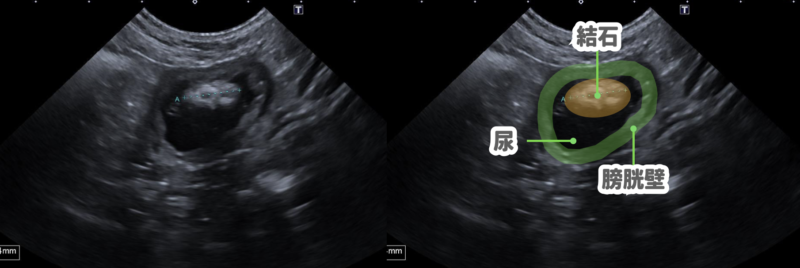

実際の症例

8歳の去勢オスのヨークシャテリアが嘔吐、下痢の相談に来院されました。

この来院時の検査にて偶然、膀胱結石を見つけることができました。

嘔吐下痢の検査とともに、尿の検査も行いました。

尿検査では出血が認められ、菌や炎症細胞も多数確認されました。

今回の検査では明らかな結晶成分が認められず、ストルバイト結石かシュウ酸カルシウム結石かを診断することは困難でした。

出血や尿もれが日常的に起こっていることから、この症例が膀胱炎で日常生活に支障が出ていると判断し、嘔吐・下痢の治療が終了したのち、摘出手術を行いました。

結果はリン酸アンモニウムマグネシウム(ストルバイト)でした。